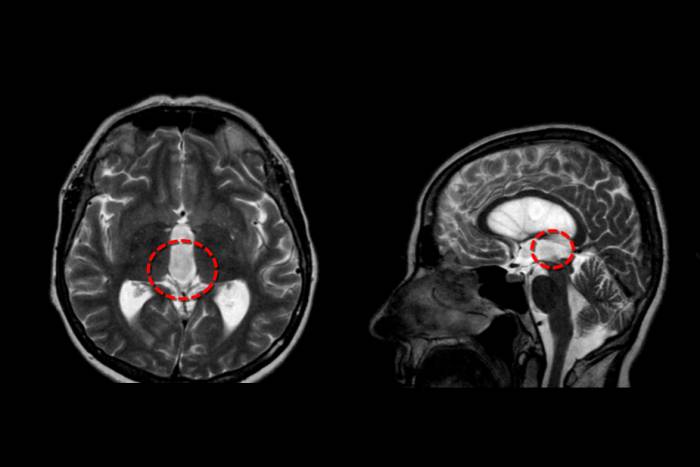

Врачи подчеркивают, что признаки опухоли головного мозга могут варьироваться в зависимости от ее типа и расположения. Наиболее распространенные симптомы включают головные боли, изменения в зрении, слухе и координации, а также проблемы с памятью и концентрацией. Важно отметить, что эти проявления могут быть вызваны и другими заболеваниями, поэтому диагностика требует комплексного подхода. Современные методы, такие как МРТ и КТ, позволяют точно определить наличие опухоли и ее характеристики. Лечение зависит от стадии заболевания и может включать хирургическое вмешательство, радиотерапию и химиотерапию. Врачи акцентируют внимание на важности ранней диагностики, так как это значительно повышает шансы на успешное лечение и улучшение качества жизни пациентов.

- МРТ (магнитно-резонансная томография);

- КТ, ангиография;